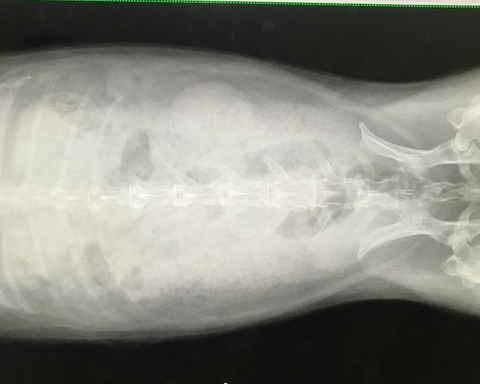

で、お歳、なこともあるのか呼吸の様子も少し気になってたので、

念のためのレントゲンをお願いしました。

胸、お腹、諸々特に問題視する箇所はありませんでした